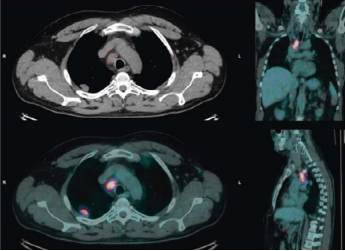

患者,男性,62岁。主因“咳嗽、呼吸困难1月”就诊,予抗感染、皮质激素治疗,症状无缓解;吸烟史20年,ECOG评分1分。CT提示右肺上叶结节(22mm),同侧气管旁淋巴结肿大(23mm)。PET/CT提示右肺上叶结节、同侧气管旁淋巴结高摄取,临床分期T1c N2 M0(stage ⅢA,eighth AJCC)。

患者的PET/CT影像